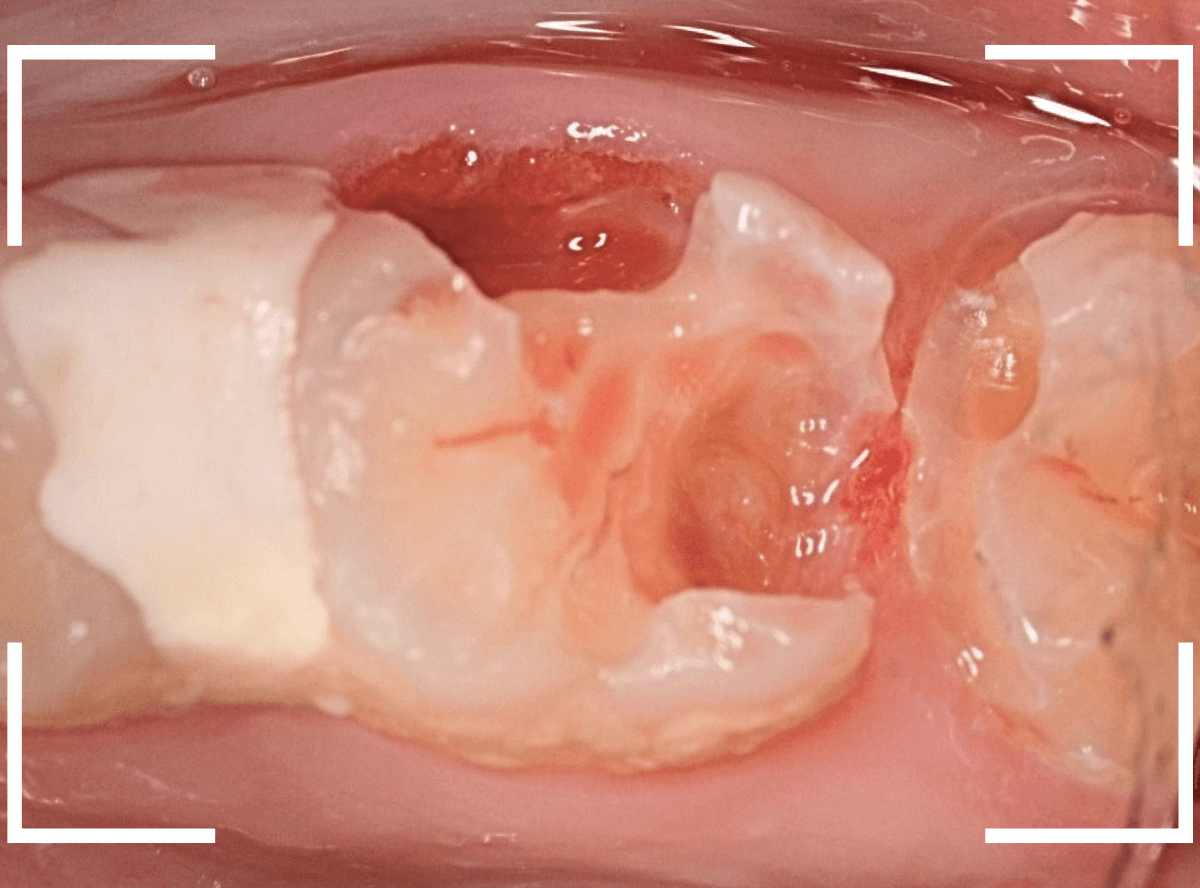

Case.22 痛みはないけど、歯のすきまから大きな虫歯

上の小臼歯の間が虫歯になっていた患者さんです。

症状はありませんし、見た目からも虫歯があるかはわかりませんでした。

レントゲン写真で確認します。

赤い線が虫歯、青い線が歯の神経です。

歯のすきまから両側に虫歯が大きく広がっているのが確認できます。

治療を開始します。

少し削ると、中からすぐに虫歯が出てきました。

ある程度、虫歯を除去したところで、う蝕検知液で確認します。

赤く染まっている部分が虫歯です。

まだまだ虫歯が中で残っている状況で、かなり深い虫歯なのが確認できます。

全ての虫歯を除去しました。

レントゲン写真からある程度確認出来ましたが、歯の神経スレスレまで虫歯が進行していました。

ここまで虫歯が進行していても、全く症状を感じない事も多いです。